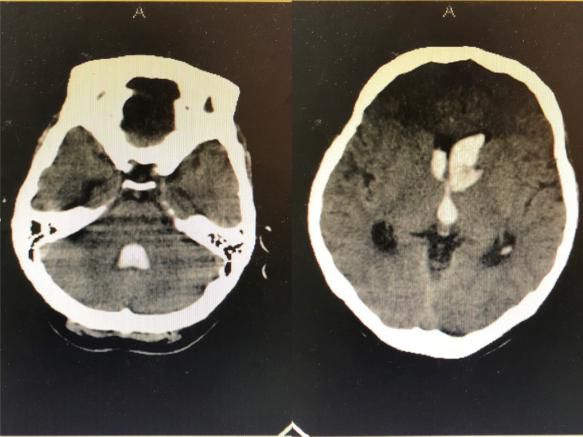

2018年9月3日,一位突发昏迷的患者被推到了神经外科病区。头颅CT提示脑出血破入脑室,合并急性脑积水,必须立即手术。当医生和患者家属提到手术时候,患者家属确实欲言又止,犹豫不决,询问患者家属后得知患者父母已故,也没有子女,唯一的亲人就是姐姐,患者与姐姐都没有工作,仅靠着姐姐的低保维持生活,如今听到要手术,姐姐不知如何是好。时间不等人,如果再拖延时间患者可能因急性脑积水失去生命,神经外科王刚副主任告诉患者家属先做手术抢救生命,钱以后再说,手术顺利进行,术后患者转入重症监护室。